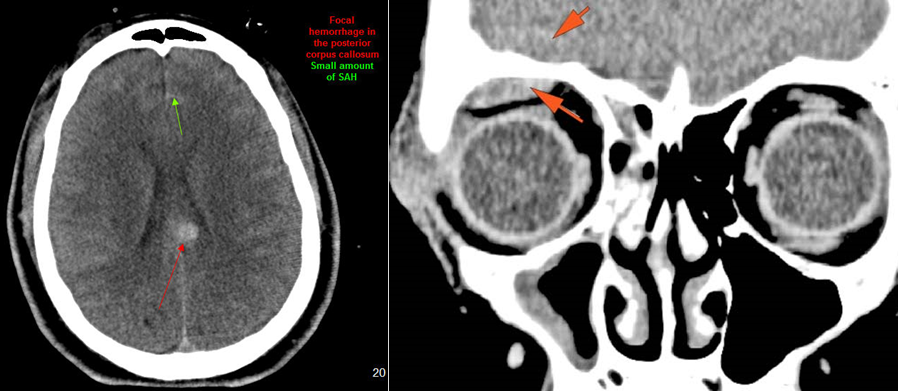

There is subperiosteal, epidural or subdural hematoma and/or pneumocephalus along the boney walls of the anterior or middle cranial fossa or elsewhere. [Yes/No]

There is subarachnoid bleeding. [Yes/No]

There is evidence of parenchymal brain injury. [Yes/No]